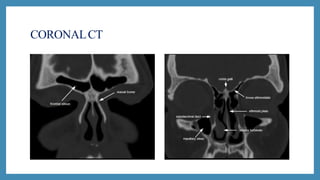

CT scan

 CT scans: Excellent views of the sinuses, best for osteomeatal

complex and ethmoidal disease

 “Limited CT Evaluation” – slice 3-4 mm

 CT navigation:

 A computer is used to identify the 3- dimensional location of a

probe tip placed within the patient's nose or sinuses..

 Improves anatomical identification and avoid damage to vital

neighbouring structures such as the brain and eyes.

CORONALCT

CT scan  CTscans: Excellent views of the sinuses, best for osteomeatal complex and ethmoidal disease  “Limited CT Evaluation” – slice 3-4 mm  CT navigation:  A computer is used to identify the 3- dimensional location of a probe tip placed within the patient's nose or sinuses..  Improves anatomical identification and avoid damage to vital neighbouring structures such as the brain and eyes.